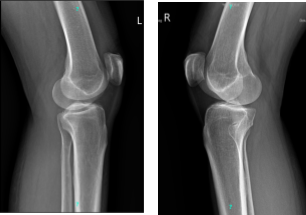

She presented X-ray which showed no fracture or post fracture deformity. Preserved joint spaces. No osteophytes or erosions. Unremarkable soft tissue structures for both knees.

X-ray Bilateral Knees 3 views each